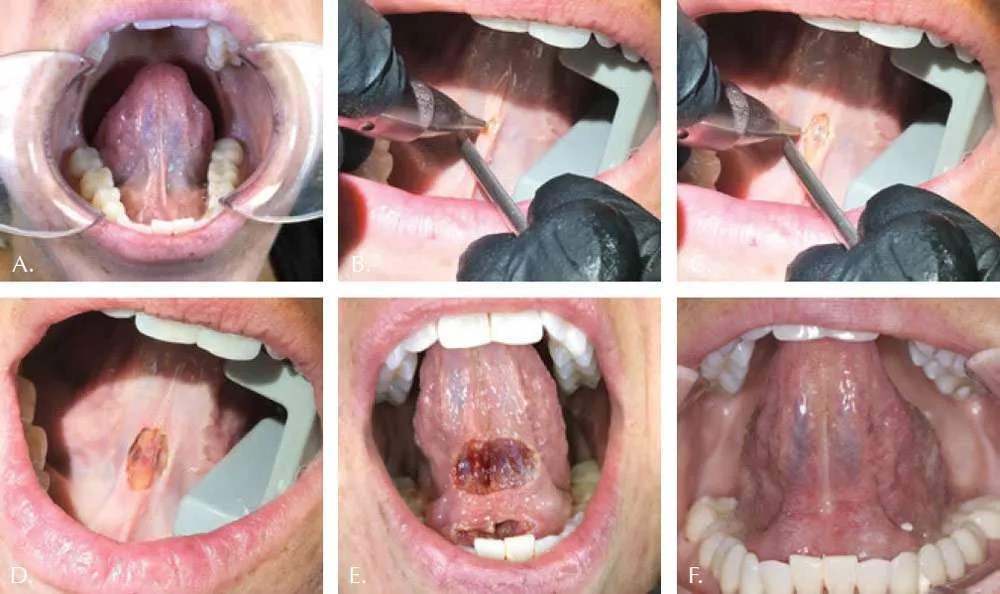

An oral and maxillofacial surgeon (oms) typically performs a frenectomy to increase the range of motion of the tongue. A frenectomy is an oral procedure during which a frenum in the mouth is altered or removed with a laser. In such conditions, a frenectomy is a good choice to preserve the good strength and aesthetics of the individual.

A frenectomy, according to the american association of oral and maxillofacial surgeons, is a simple surgical procedure where an oral surgeon releases the frenulum bands. It stabilizes dentures among denture users. A frenectomy is an oral procedure during which a frenum in the mouth is altered or removed with a laser.

A frenotomy/frenulotomy is a simple incision into the connective tissue at the bottom of the tongue to free the tongue from the floor of the mouth. A frenectomy is a small surgical procedure that removes extra soft tissue from inside your mouth. The point of having a frenectomy is to give your tongue and/or lip(s) more range of motion.